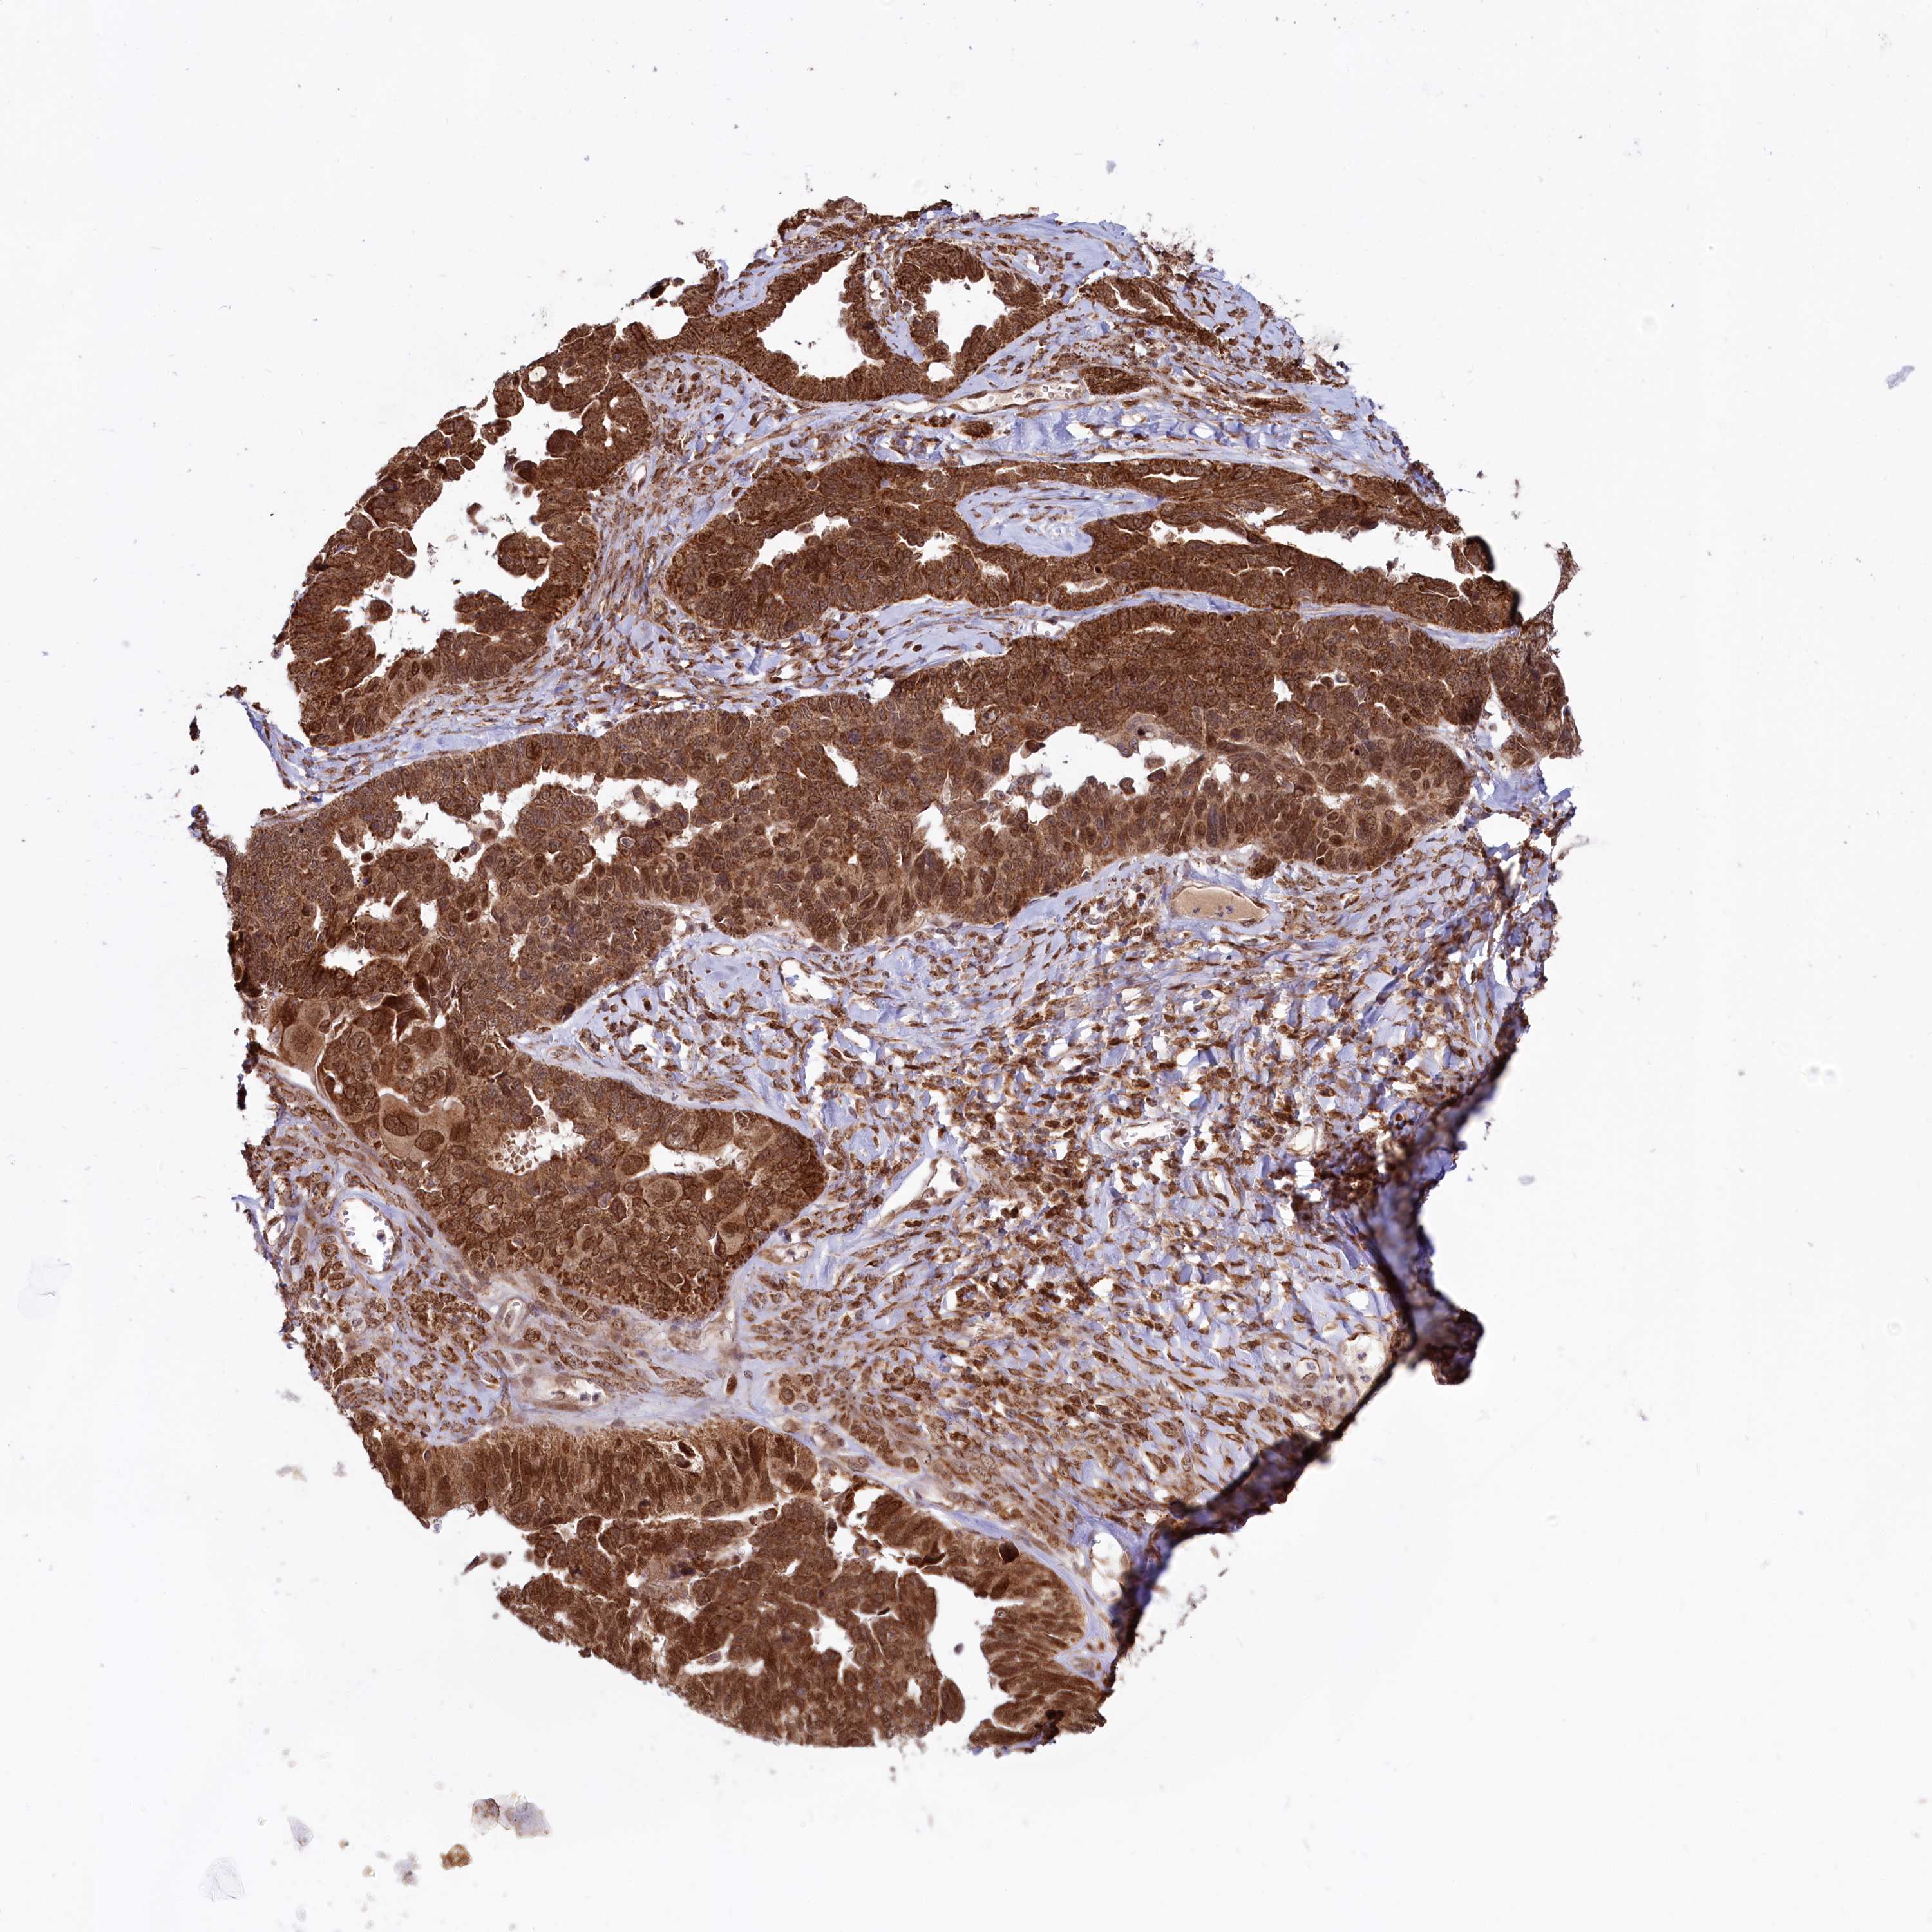

OVARIAN CANCER - Protein expressioni

A mouse-over function shows sample information and annotation data. Click on an image to view it in a full screen mode. Samples can be filtered based on level of antibody staining by selecting one or several of the following categories: high, medium, low and not detected. The assay and annotation is described here.

Note that samples used for immunohistochemistry by the Human Protein Atlas do not correspond to samples in the TCGA dataset.

Antibody stainingi

Antibody staining in the annotated cell types in the current human tissue is reported as not detected, low, medium, or high, based on conventional immunohistochemistry profiling in selected tissues. This score is based on the combination of the staining intensity and fraction of stained cells.

Each image is clickable and will lead to virtual microscopy that enables deeper exploration of all samples and also displays staining intensity scores, fraction scores and subcellular localization as well as patient and tissue information for each sample.

Antibody HPA039162

Staining

High

Medium

Low

Not detected

Intensity

Strong

Moderate

Weak

Negative

Quantity

>75%

75%-25%

<25%

None

Location

Nuclear

Cytoplasmic/membranous

Cytoplasmic/membranous,nuclear

Cystadenocarcinoma, serous, NOS

Carcinoma, endometroid

Cystadenocarcinoma, mucinous, NOS

Carcinoma, NOS